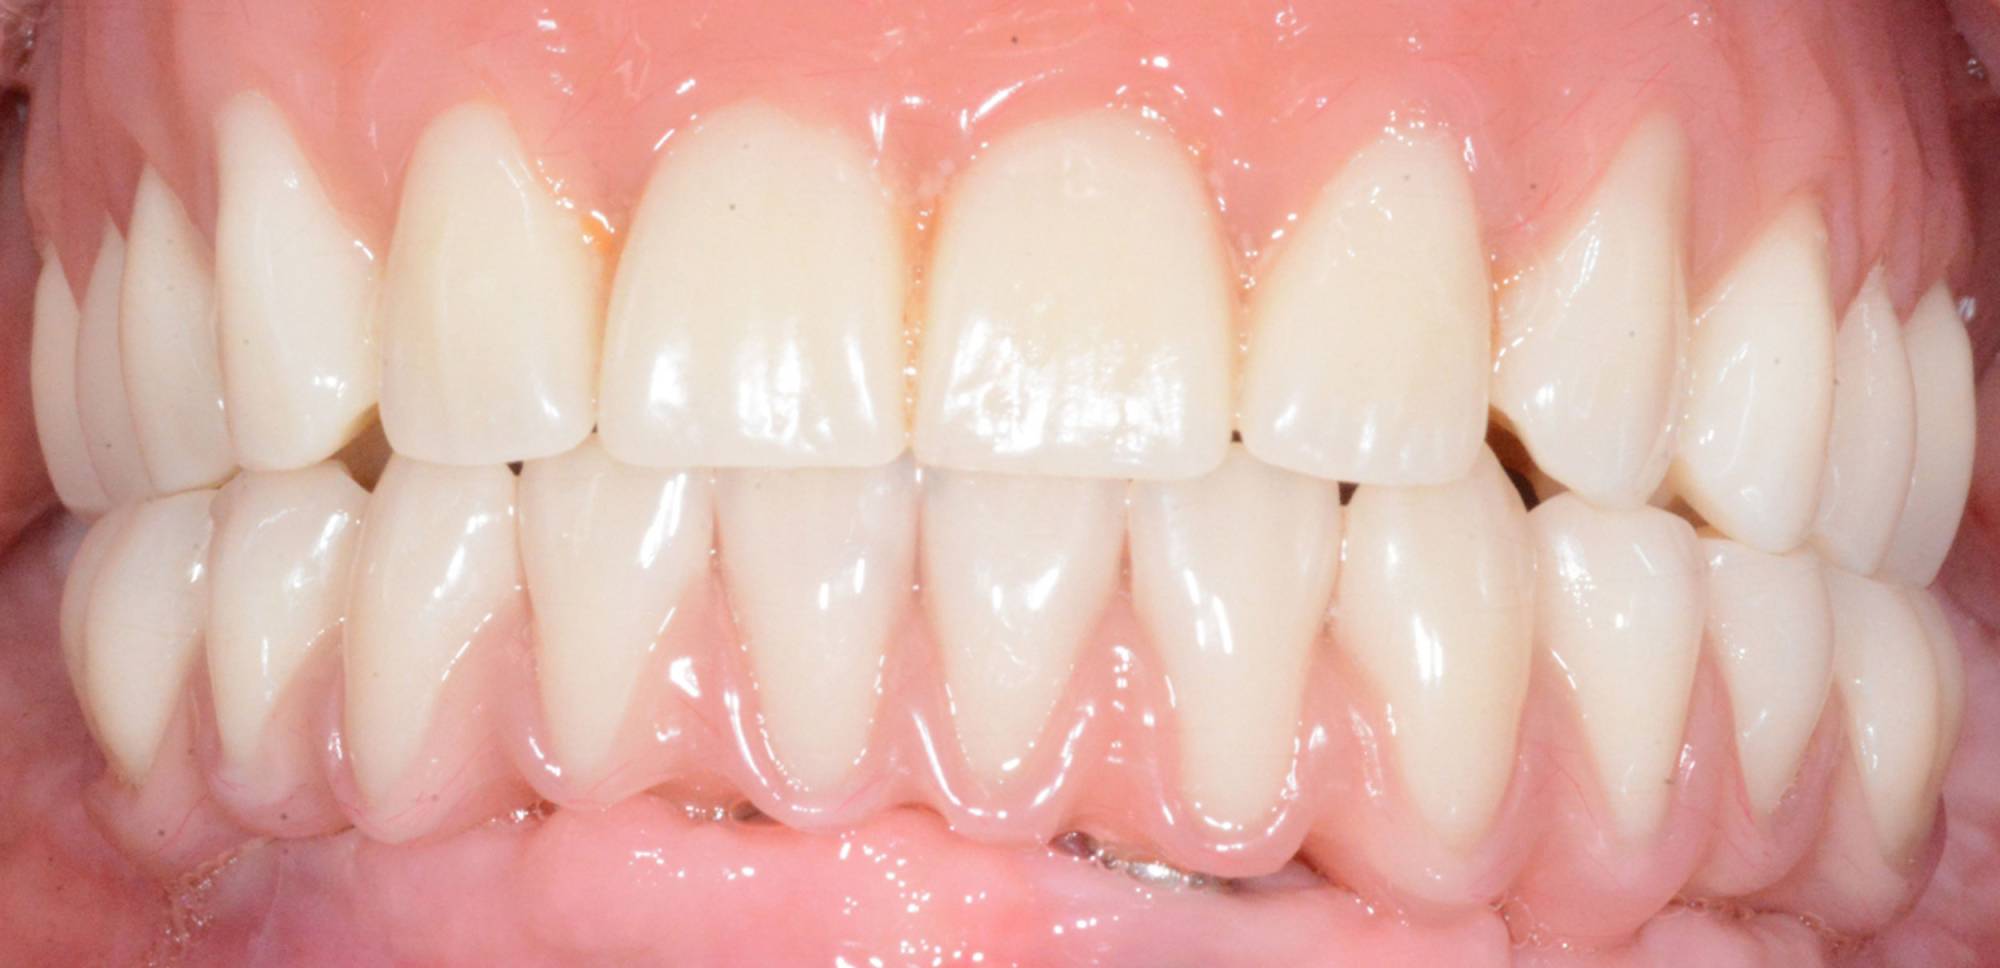

L'impianto, oltre a essere un metodo sicuro, garantisce l'aspetto esteriore e la piena funzionalità di un dente naturale. Oltre a ciò, mantiene l’integrità dell’osso, non va ad intaccare i denti adiacenti - come invece farebbe un ponte - e migliora l’estetica facciale prevenendo la perdita ossea.

Gli impianti sono molto versatili e possono essere usati per sostituire un dente singolo, più denti fissi o addirittura un'intera arcata. Inoltre, possono essere inseriti sotto una protesi mobile per stabilizzarla migliorandone il comfort.